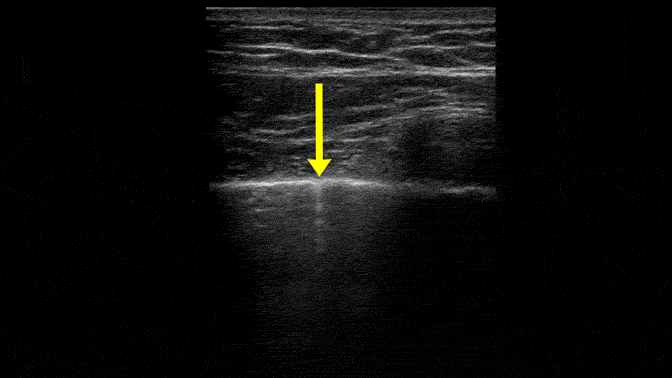

Comet Tail Artifact – a common finding in normal lung

These are comet tail artifacts. Notice that they are short and diminish in brightness over a few centimeters